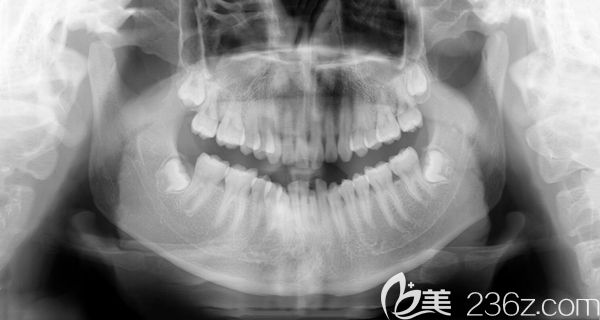

男朋友牙齒太難看,分享和他去廣州陽(yáng)光樹口腔做門牙齙牙深覆蓋矯正后臉型變化圖 b1557 G0 V0

男朋友牙齒太難看了,給大家分享下他在廣州陽(yáng)光樹口腔做門牙齙牙矯正+牙齒排列不齊的深覆蓋臉型變化圖,快來看看他現(xiàn)在變成什么樣了。